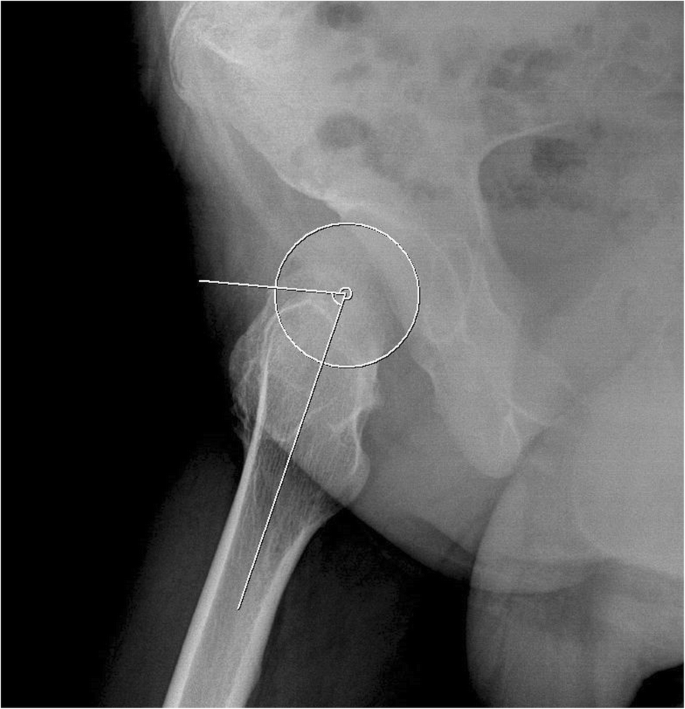

Patients were classified into the FAI and IFI symptom groups by comparing the correlation with symptoms, physical exam and imaging studies. On FAI symptom patients evaluation, the patients who had a groin pain during the hip flexion, abduction and rotation, and had a corresponding images matched by alpha angle (Fig. 1) were defined as having FAI symptom. Whereas, the IFI symptom group defined as the patients who complained hip discomfort during hip extension, adduction, and rotation with a significant reduction of the minimum ischio-femoral distance on hip CT evaluation [18]. The patients who did not meet the FAI or IFI symptom were classified to non-symptom group.

Morphometric analysis

Radiographic analysis was conducted using the last follow-up radiographs in patients who had not undergone any surgical intervention, and the last preoperative radiographs in those who had undergone surgical treatment around the hip joints. For the morphometry of the hip joint in patients with MHE, the femoral neck-shaft angle of Muller [19] was evaluated to assess proximal femur deformity, and Sharp’s acetabular angle [20] and the center-edge (CE) angle [21, 22] were evaluated to assess the deformities of acetabulum (Fig. 2). For FAI evaluation, alpha angle (Fig. 2) of all hips was measured regardless of the presence or absence of symptoms. For IFI evaluation, hip CT studies in patients with MHE were performed in the neutral supine position and the nearest distance between the exostoses and ischium around the lesser trochanter area were measured at axial plane (Fig. 3).